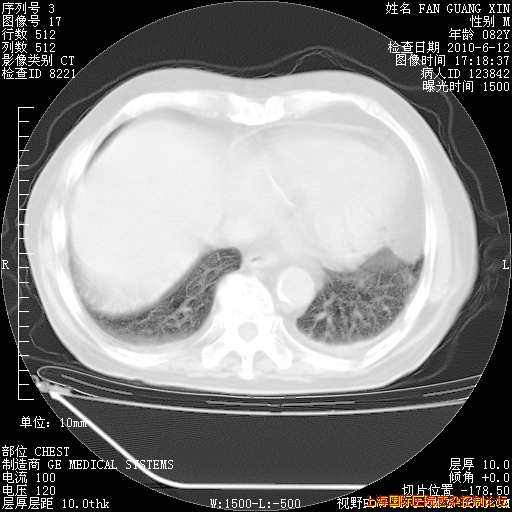

6月12日肺窗

整整相隔30天的肺部CT好像有所好转啊。甲强龙减量第3天,需要观察体温。